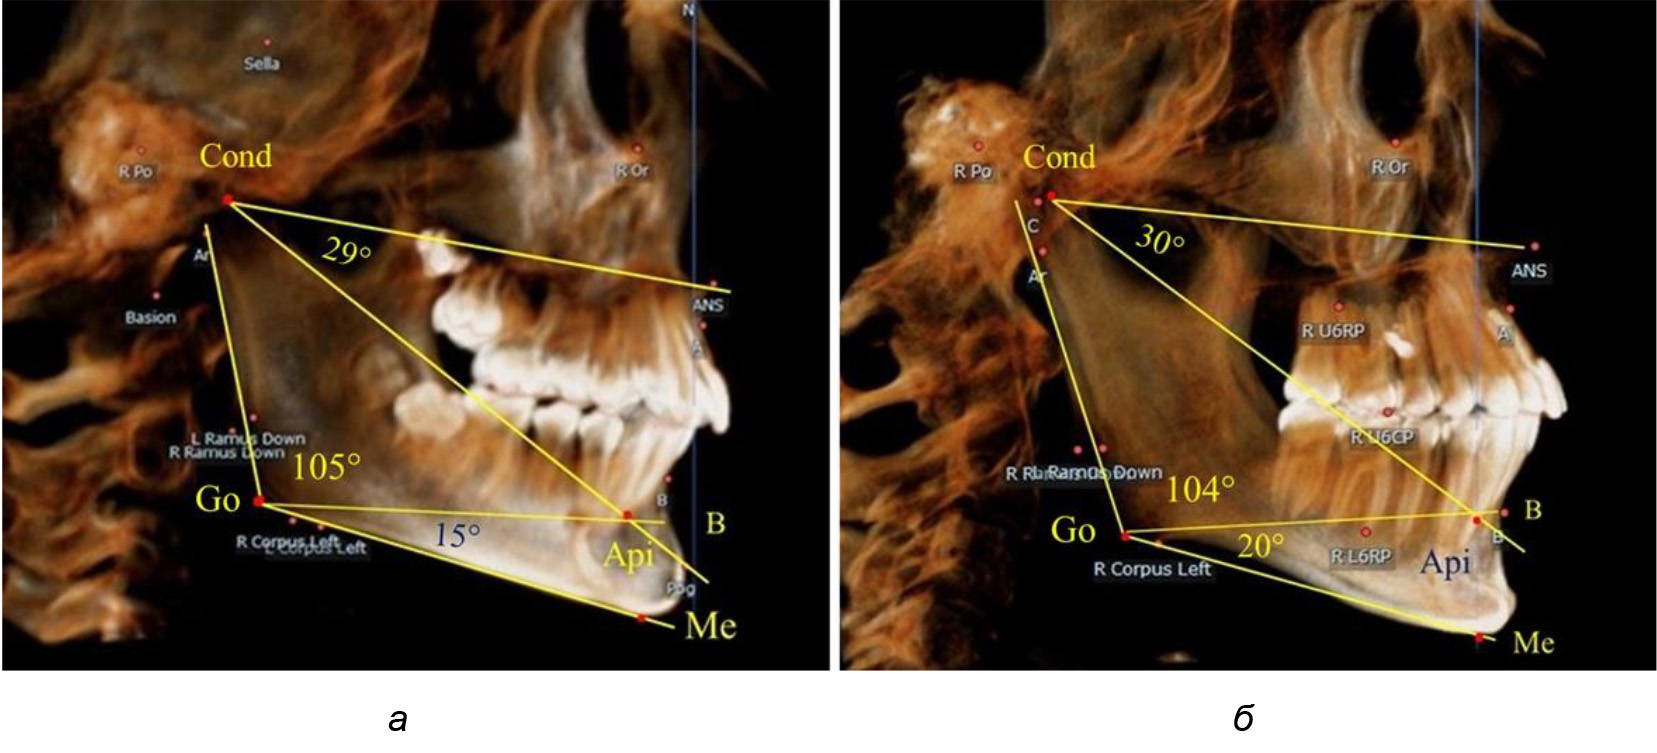

При анализе ТРГ 5 детей в периоде прикуса молочных зубов отмечено, что величина основного угла гнатической части лица SNA-Cond-Api, как правило, в норме составляла около 30°, и его величина была относительно стабильной у всех обследованных детей. В то же время угол нижней челюсти и его составляющие отличались вариабельностью параметров при различных показателях нижнечелюстного угла (рис. 4).

Рис. 4. Особенности ТРГ (а) и 3D-модели (б) в периоде прикуса молочных зубов

Таким образом, в периоде молочного прикуса с оптимальными окклюзионными соотношениями, несмотря на линейные размеры в вертикальном и сагиттальном направлении, которые, безусловно, меньше параметров взрослых людей, величина основного угла гнатической части лица SNA-Cond-Api соответствовала параметрам людей с полностью сформированным физиологическим прикусом постоянных зубов. Анализируя данные рентгенограмм детей в периоде сменного прикуса, отмечено, что величина основного угла гнатической части лица SNA-Cond-Api, так же как в молочном и постоянном прикусе, в норме составляла от 28 до 32°. В то же время угол нижней челюсти и его составляющие отличались вариабельностью параметров при различных показателях нижнечелюстного угла. Достоверных различий угла гнатической части после смены нижних медиальных резцов и прорезывания первых постоянных моляров (4 ребенка) не было; происходил очередной этап подъема высоты прикуса и увеличение линейных размеров костей гнатической части, однако угловые параметры были относительно стабильны. После смены всех резцов и замены первых молочных моляров первыми премолярами (6 человек) увеличивались линейные размеры при сохранившихся угловых показателях гнатической части лица (рис. 5).

После смены всех молочных зубов (анализ 9 ТРГ) и после прорезывания вторых постоянных моляров (7 человек) происходил очередной этап подъема высоты прикуса с увеличением размеров костей гнатической части лица. Однако величина основного угла гнатической части лица SNA-Cond-Api, так же как в молочном и сменном прикусе, в норме составляла (30,02 ± 1,25)°, что не имело достоверных различий (р ˃ 0,05) с аналогичным параметром, анализируемом в других группах исследования. Угол нижней челюсти и его составляющие отличались вариабельностью параметров при различных показателях нижнечелюстного угла (рис. 6).

Рис. 6. Варианты 3D рентгенограмм детей после смены всех молочных зубов (а) и после прорезывания вторых моляров (б)